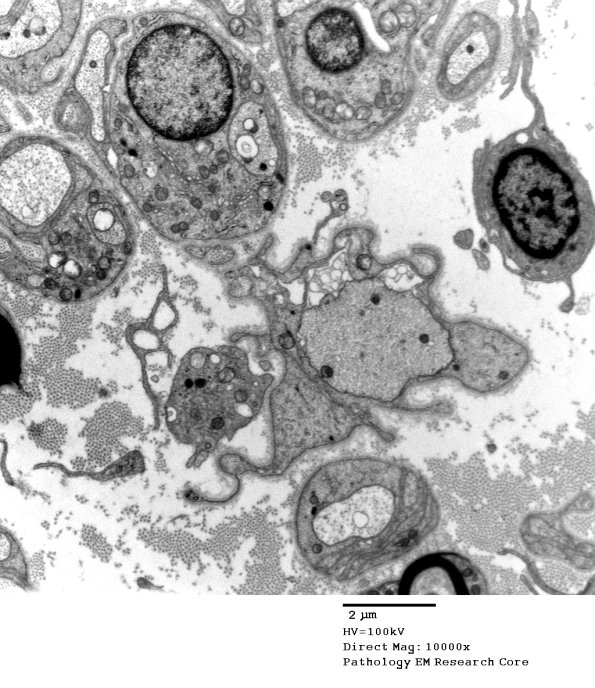

3B6-9 Multiple examples of naked and remyelinating axons. (electron micrographs)